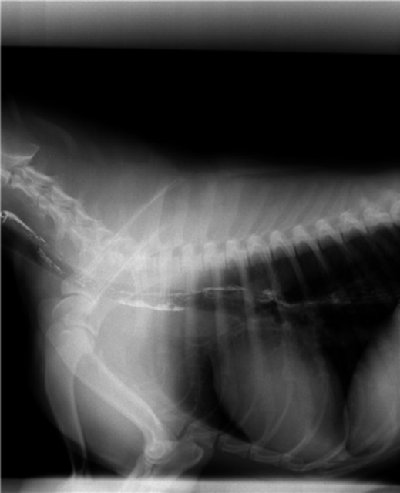

Дивертикул прямой у собак

Дивертикул прямой у собак 110 фото